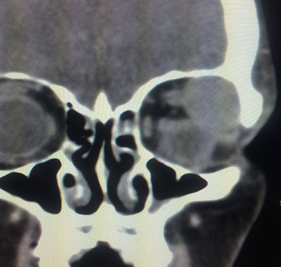

Orbital Infection/Inflammation

Orbital cellulitis is an orbital infection of the soft tissues within the eye socket. It is most often due to an extension of infection from nearby sinuses. It can also be caused by direct infection following local injury such as insect bite and penetrating eyelid injuries. Spread of infection from the face or teeth via blood can also be the cause. Patients may present with blurred vision, double vision, eye pain, bulging eye, eyelid swelling and redness. Fever may accompany the other symptoms. Diagnosis is based on history, clinical examination and imaging such as CT scan or MRI. First line of treatment is systemic antibiotics and sometimes surgical drainage may be required.